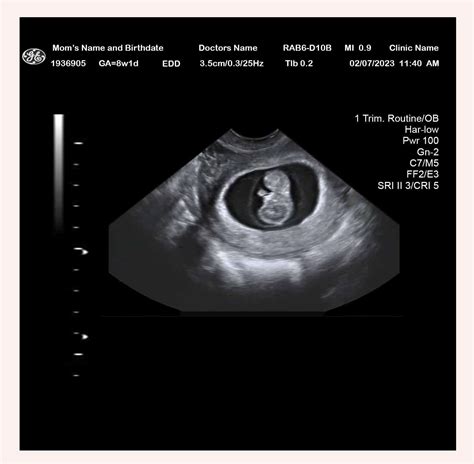

• baby at 8 weeks gestation

• 8 weeks pregnant baby development

• baby 8 weeks pregnant pictures